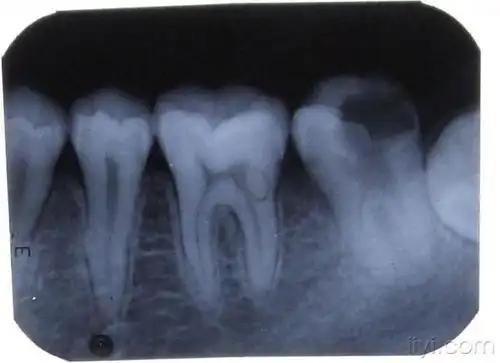

牙片

我也来晒晒我的牙片请大佬来看看07怎么样

69 口腔医学专业讨论版 69 根尖处这样大的阴影《附牙片》要怎么